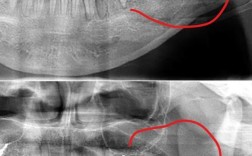

拔尖牙并非常规操作,仅适用于特定病例,需通过模型分析、X线片(全景片、头颅侧位片)等检查综合判断,以下是常见的拔尖牙适应症,可通过表格更直观理解:

| 尖牙位置异常 | 尖牙埋伏、阻生,或萌出方向异常(如腭向、垂直萌出),无法通过正畸牵引排齐 | 尖牙完全埋于颌骨内,靠近鼻腔,正畸导萌失败后,为避免损伤邻牙和牙槽骨,需拔除 |

- 术前评估:需拍摄CBCT(锥形束CT)确认尖牙牙根形态、位置及与邻牙、神经的关系,避免拔牙损伤;